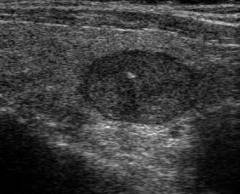

- Фолликулярная аденома. Представляет собой узел округлой формы, покрытый капсулой.

Отличить один вид аденомы от другого можно только при исследовании фрагмента новообразования под микроскопом. Выделяется среди прочих разновидностей своими симптомами только токсическая аденома щитовидной железы.

Чаще при аденоме в толще железы обнаруживается один узел. Реже встречаются множественные узлы.